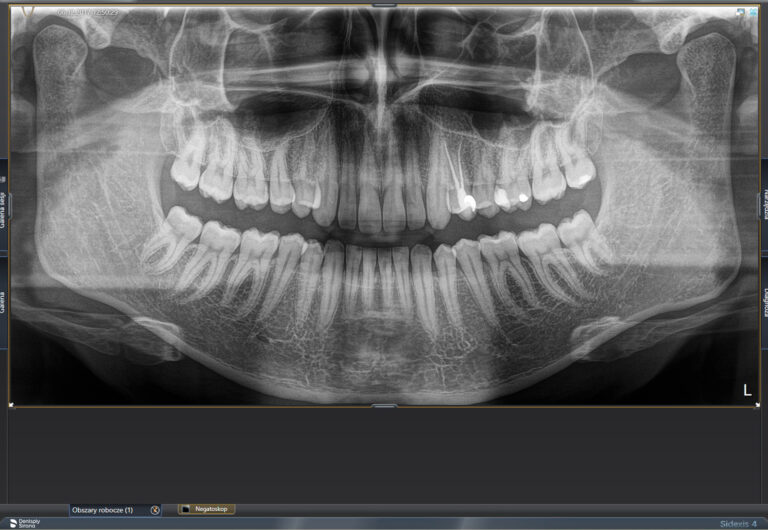

W naszych gabinetach oferujemy wykonanie wielu rodzajów zdjęć rtg. Są to nieinwazyjne badania obrazowe uzupełniające diagnostykę, w związku z czym na pierwszej wizycie zwykle wykonywane jest zdjęcie panoramiczne zębów. Pozwala ono ocenić stan wszystkich zębów i tkanek okolicznych.

Zdjęcia ortopantomograficzne ( nazywane panoramicznymi),